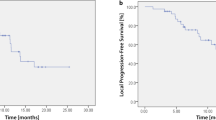

All patients were followed for at least 23 months or until their death. The 1-year, 2-year, and 3-year OS rates were 97.1% (95% CI: 91.6–100%), 74.3% (95% CI: 59.8–88.8%), and 67.2% (95% CI: 50.3–83.3%), respectively (Fig. 1). The median survival time was 56 months (95% CI: 33.1–78.9 months). The 3-year cancer specific survival rate was 76.3% (95% CI: 60.4–92.2%). Nine patients died due to lung cancer (metastasis, n = 7; local recurrence, n = 2), and 8 patients died due to other causes (another newly diagnosed cancer after PBT, n = 4; other diseases, n = 4). The 3-year OS rate was significantly different between operable and inoperable patients (90% vs 58.2%, p = 0.008) (Fig. 2).

The 3-year local control rate was 86.5% (95% CI: 74.0–99.0%) (Fig. 3). Four patients had local recurrence at 9–33 months. Two had lymph node metastasis, 6 had lung metastasis outside of the PBT field. Regarding other organ metastasis, 1 patient had liver metastasis, 1 patient had brain metastasis, and 4 had pleural dissemination.